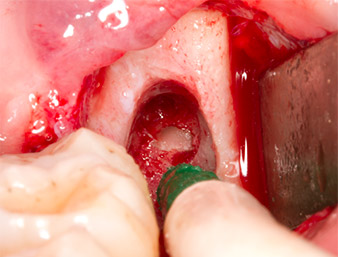

The tissue above the root remnant was not completely ossified and consisted for the most part of granulation tissue modified by inflammation (Fig.4).

Granulation tissue

Fig. 4: Two Langenbeck retractors and a raspatorium expose the operating area. Granulation tissue of the incompletely healed first osteotomy can be seen.